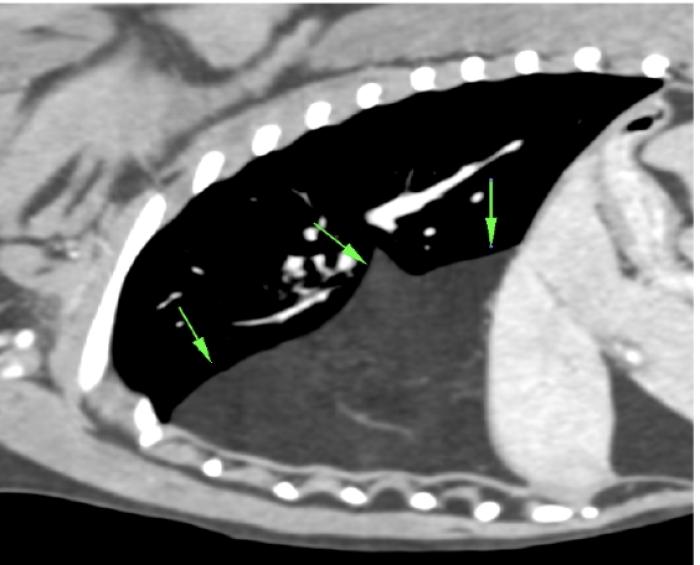

El espacio en situaciones patológicas puede estar ocupado no sólo por aire o fluido, ecográficamente podemos detectar órganos abdominales que ante una rotura diafragmática que se traslocan cavidad torácica, la presencia de masas con origen en linfonodos, timo, neoplasias de la pared torácica, etc. y comprometen la distensión pulmonar por volumen que ocupan (Figura 11A-B) (Vídeo 7).

Signo de cuña

Se trata de una consolidación de aspecto triangular o trapezoidal cuya base se encuentra en la LP. Los bordes son más regulares que en el caso del signo de fragmentación, no presentan broncogramas aéreos y si es factible utilizar el Doppler veremos ausencia de flujo en el foco afectado. Comúnmente pueden ir asociados a efusión pleural y si el cuadro respiratorio es agudo, la causa más frecuente es el tromboembolismo pulmonar.

Existe cierta controversia con respecto a si en perros y gatos este signo se describe con aspecto triangular como ocurre en los humanos, puesto que anatómicamente hay diferencias con respecto a la sección menos triangular que describe la vasculatura y por tanto quizá sea más correcto hablar de un aspecto trapezoidal del área consolidada (como se visualiza en la figura 15.3) que puramente triangular (Figura 15A-D).